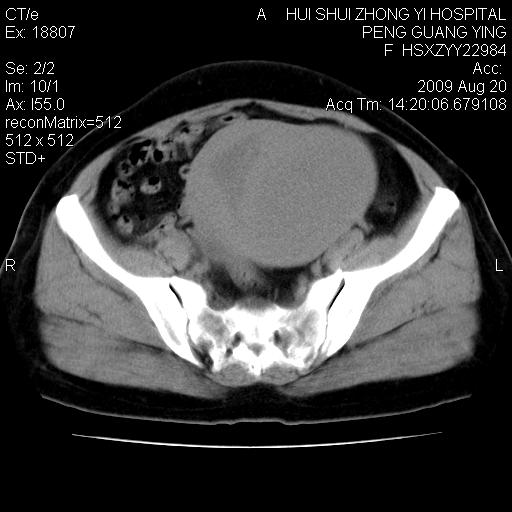

标题: CT21707:女,42岁,因发现下腹部包块2月。 [打印本页]

标题: CT21707:女,42岁,因发现下腹部包块2月。

目前的影像表现显示肿块位于腹腔及盆腔,但具体定位,分清来源较困难,是否来源于卵巢、子宫无法定论,子宫直肠及子宫膀胱周围脂肪间隙尚较清晰,如果患者有过腹腔好或者盆腔手术史,也可以形成不典型的血中,最好手术后定为定性,我期待结果。

软组织密度,与子宫一致。双侧卵巢形态、密度好,不支持来源于卵巢。

病史不全面,病灶来源可能是子宫或卵巢,若临床有剖腹产、痛经史,则更支持前者,亦更支持子宫腺肌症